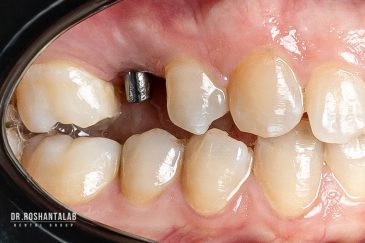

تجربه کاشت دندان دیجیتال و بدون درد در ۳ دقیقه! استفاده از برترین برندها زیر نظر جراح، با هزینه مناسب و خدمات کامل از کاشت دندان تا روکشارتودنسی دندان

انتخاب بهترین متخصص ایمپلنت که به تکنیکهای روز دنیا مسلط باشد، تضمینکننده سلامت فک و زیبایی لبخند شماست. در کلینیک دندانپزشکی دکتر روشنطلب، ما با بهرهگیری از تجهیزات دیجیتال در ۵ شعبه فعال (تهران، اصفهان، رشت و استانبول ترکیه)، خدمات تخصصی کاشت ایمپلنت دندان را برای بیمارانی که کیفیت و دقت برایشان اولویت دارد، ارائه میدهیم. در این متد، پروسه درمان با ظرافت بالا انجام شده؛ راهکاری ایدهآل برای کسانی که به دنبال درمان بدون درد با بالاترین نرخ موفقیت هستند.